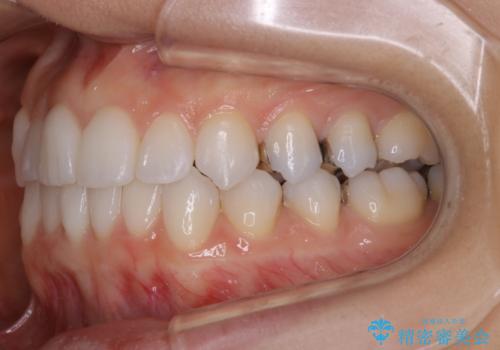

- 前歯のガタつき改善を主訴にご来院されました。

ガタつき自体は軽度で、奥歯の噛み合わせのズレもほとんどなかったため、非抜歯でマウスピース矯正装置を選択しました。

歯列の幅の拡大と歯を小さくする調整を行うことで並べるスペースの確保を行いました。この方法は、ガタつきをとりたいところに直接スペースを作ることができるので治療期間を短縮することができ効率的です。